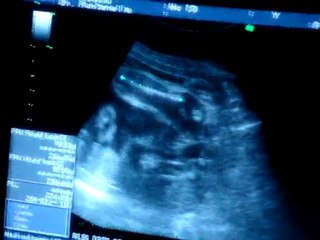

Dissection de l'aorte

Dédoublement de la paroi aortique chez un br Homme de 60 ans br Grand tabagique